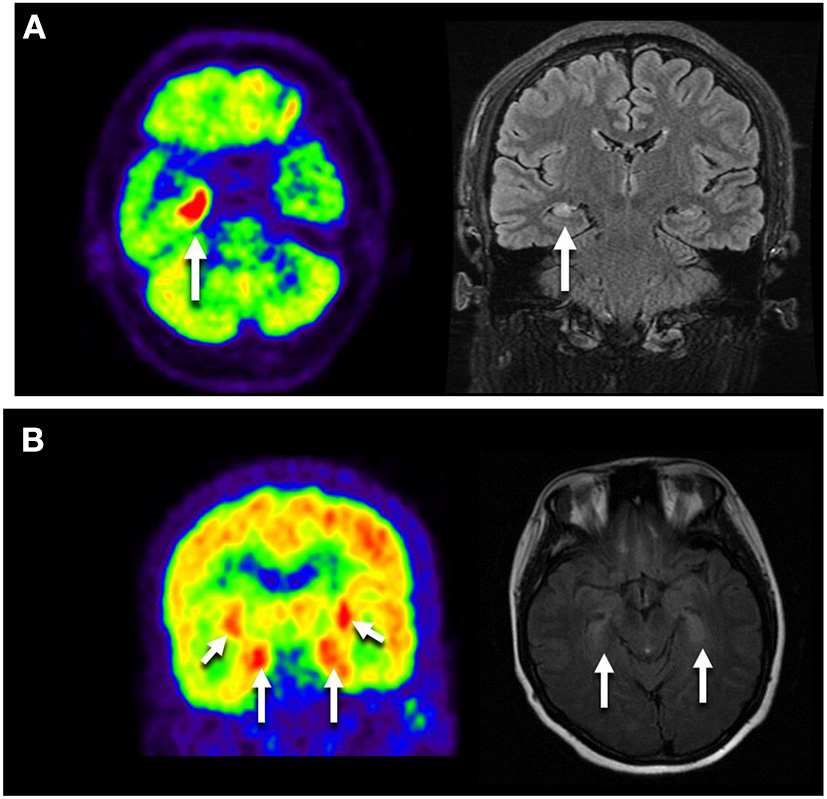

Thirteen patients completed 18F-FDG PET/CT scans: one presented with multicortical hypermetabolism, four with temporal lobe hypermetabolism, and one with cerebellar hypometabolism (Figure 2).

Figure 2

Neuroimages of the GAD65 antibody associated neurological disorders. (A) Images of NO.9 who presented with Ep. Axial FLAIR MRI showed right temporal hyperintensity, and Axial FDG-PET/CT scan showed hypermetabolic right mesiotemporal spot (white arrow). (B) Images of NO.41 who manifested as LE plus ACA. 18F-FDG PET/CT showed increased FDG uptake in the bilateral medial temporal lobes. MRI showed bilateral medial temporal lobe T2 hypertension. LE, limbic encephalitis; Ep, epilepsy; ACA, autoimmune cerebellar ataxia.